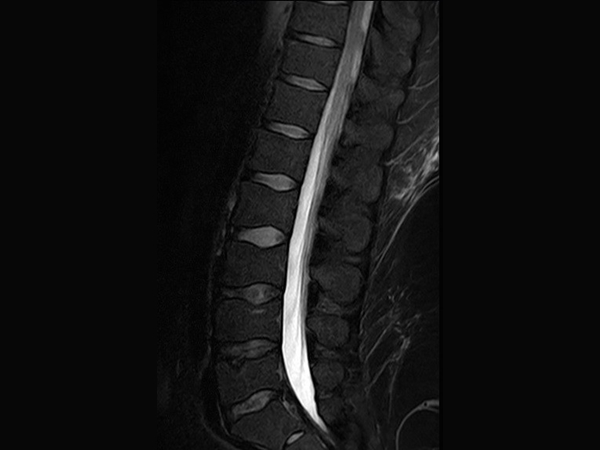

This is a lumbar spine examination of a young obese patient (170 kg) with right sciatic pain. The main difference in the protocol for this obese patient is that the voxel size is around 15-20% larger than in our standard protocol. This patient's weight will vastly increase the minimum TR requirements under the SAR modelling of any 3T scanner. The larger voxel helps both in reducing this increase in scan time and reduces SAR.The MultiTransmit technology evens out the flip angle and SAR across these large fields of view, even when filled with such a large patient, and the dStream coils and SmartSelect technology allows maximum penetration to allow for excellent SNR.The images demonstrate the high SNR provided by dStream and achieved with SmartSelect, which uses a quantitative method to determine and activate all coils that increase SNR. Imaging penetrated 150 mm of fat to reach this patient’s lower L-spine.

Sagittal T2w TSE